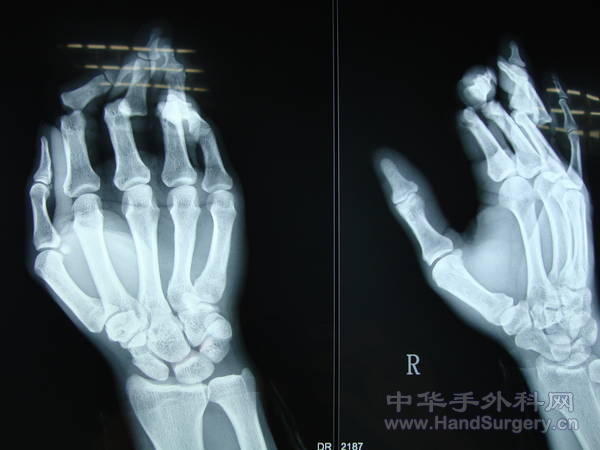

患者  男 32岁  绞伤至2-4指近指间关节开放脱位  急诊行脱位复位内固术、侧副韧带修补术,血管神经肌腱探查修补术,术后克氏针固定4周,功能锻炼历时2.5月。

食指桡侧指固有神经撕脱,与尺侧指固有神经指背支吻合。

术中复位关节后  常规修补两侧侧副韧带 及掌板   关节囊用5个0微翘线修补   术后十天后主动活动远指间关节  4周后拆除克氏针  配合中药熏洗功能锻炼